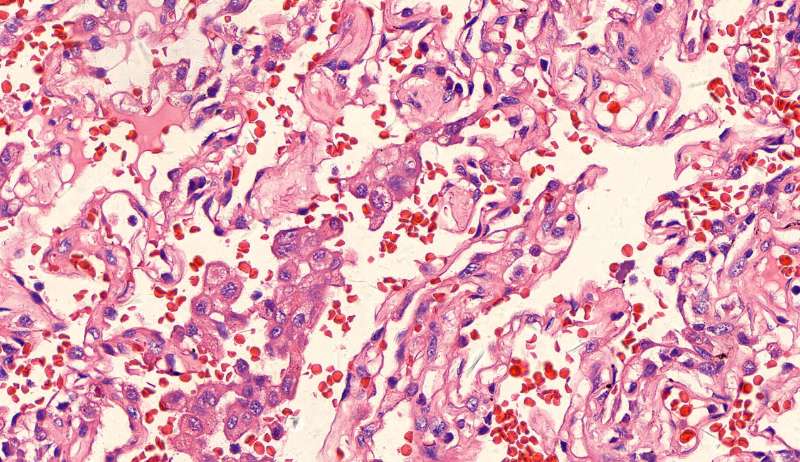

这三幅是周围区,也有巨噬细胞,单核的多 都在肺泡腔内 所以有ggo样密度 过一段时间,晕就消失,有时是消退,有时是实性区扩大,盖住磨玻璃晕 那也是吞噬的作用,常代表免疫力正常 就是警察多了把肺泡填了

前两幅是第一例

第二例也是类圆形结节状